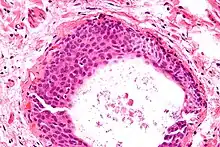

High magnification micrograph of a Brenner tumor showing the characteristic coffee bean nuclei which are also seen in Walthard cell rests. H&E stain.

They appear as white/yellow cysts or nodules that can reach a size of 2 millimeters. They typically have elliptical nuclei with a long groove (along the major axis) – so-called "coffee bean" nuclei.